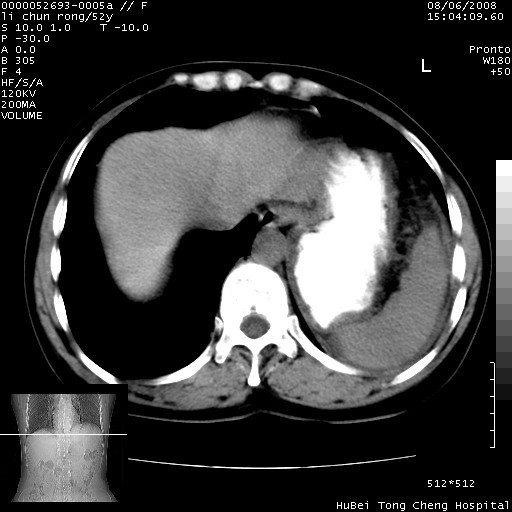

以下是引用云翔在2008-8-7 6:20:00的发言:[br]胰尾部囊性病变,考虑假囊肿,结合实验室检查疾病史

以下是引用zjzjr在2008-8-7 8:38:00的发言:[br]支持胰腺炎伴假囊肿形成,左肾小囊肿.少量腹水.

以下是引用随光逐影在2008-8-7 9:12:00的发言:[br]1)考虑胰腺炎伴假性囊肿形成可能性大;胰腺囊腺瘤待排。2)左肾小囊肿。3)少量腹水。